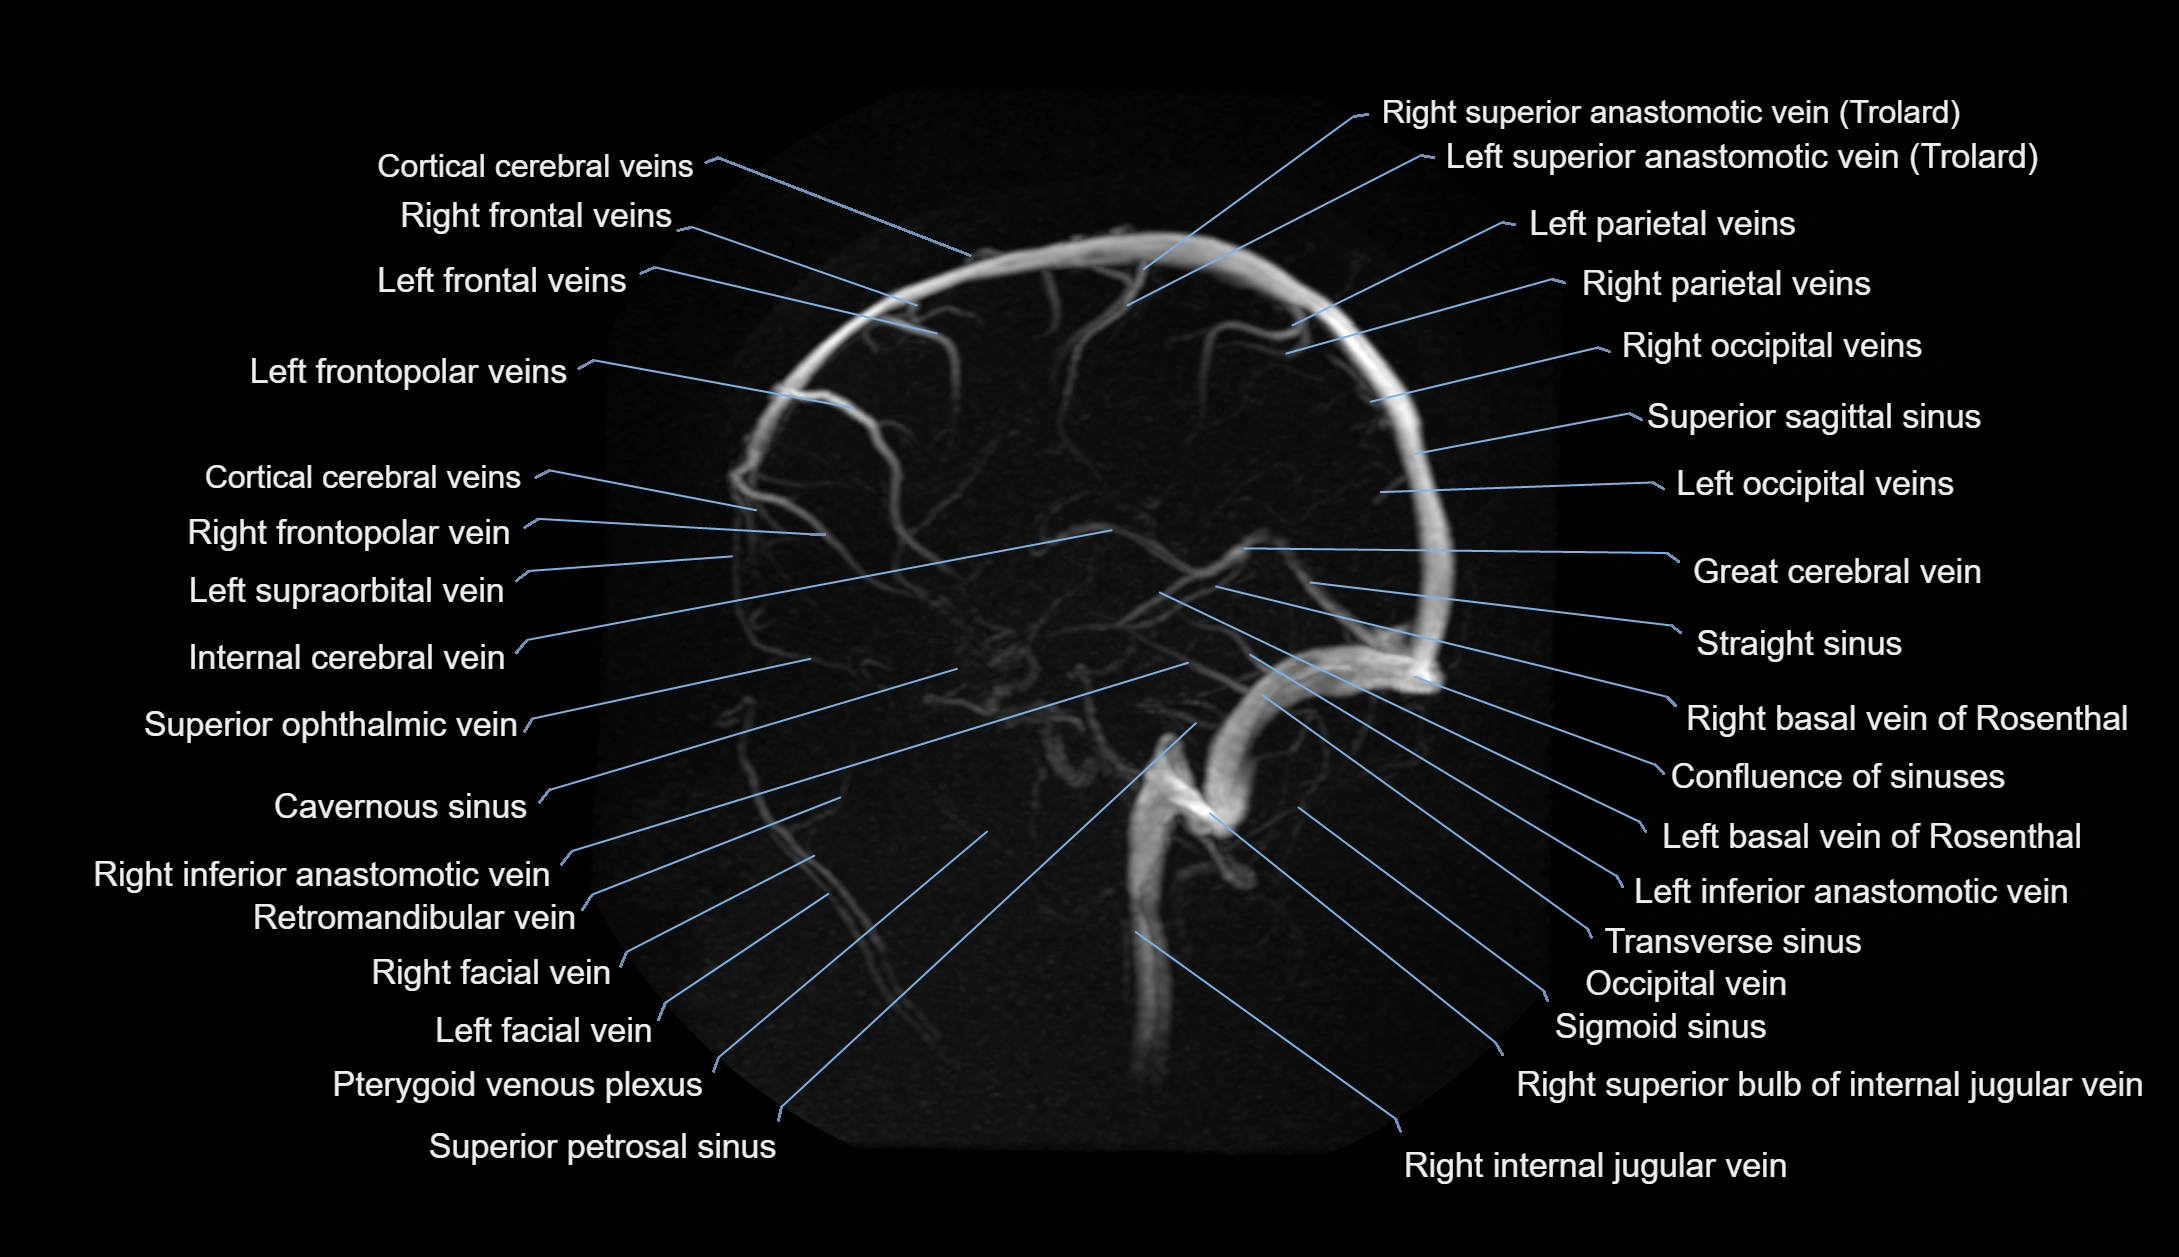

MR Venography (MRV):

• Time-of-flight (TOF) or contrast-enhanced MRV shows the angular vein as a bright enhancing venous channel

• Clearly demonstrates its continuity with the facial vein and superior ophthalmic vein

• MRV is highly useful in evaluating thrombosis, venous obstruction, or collateral venous drainage

MRI images